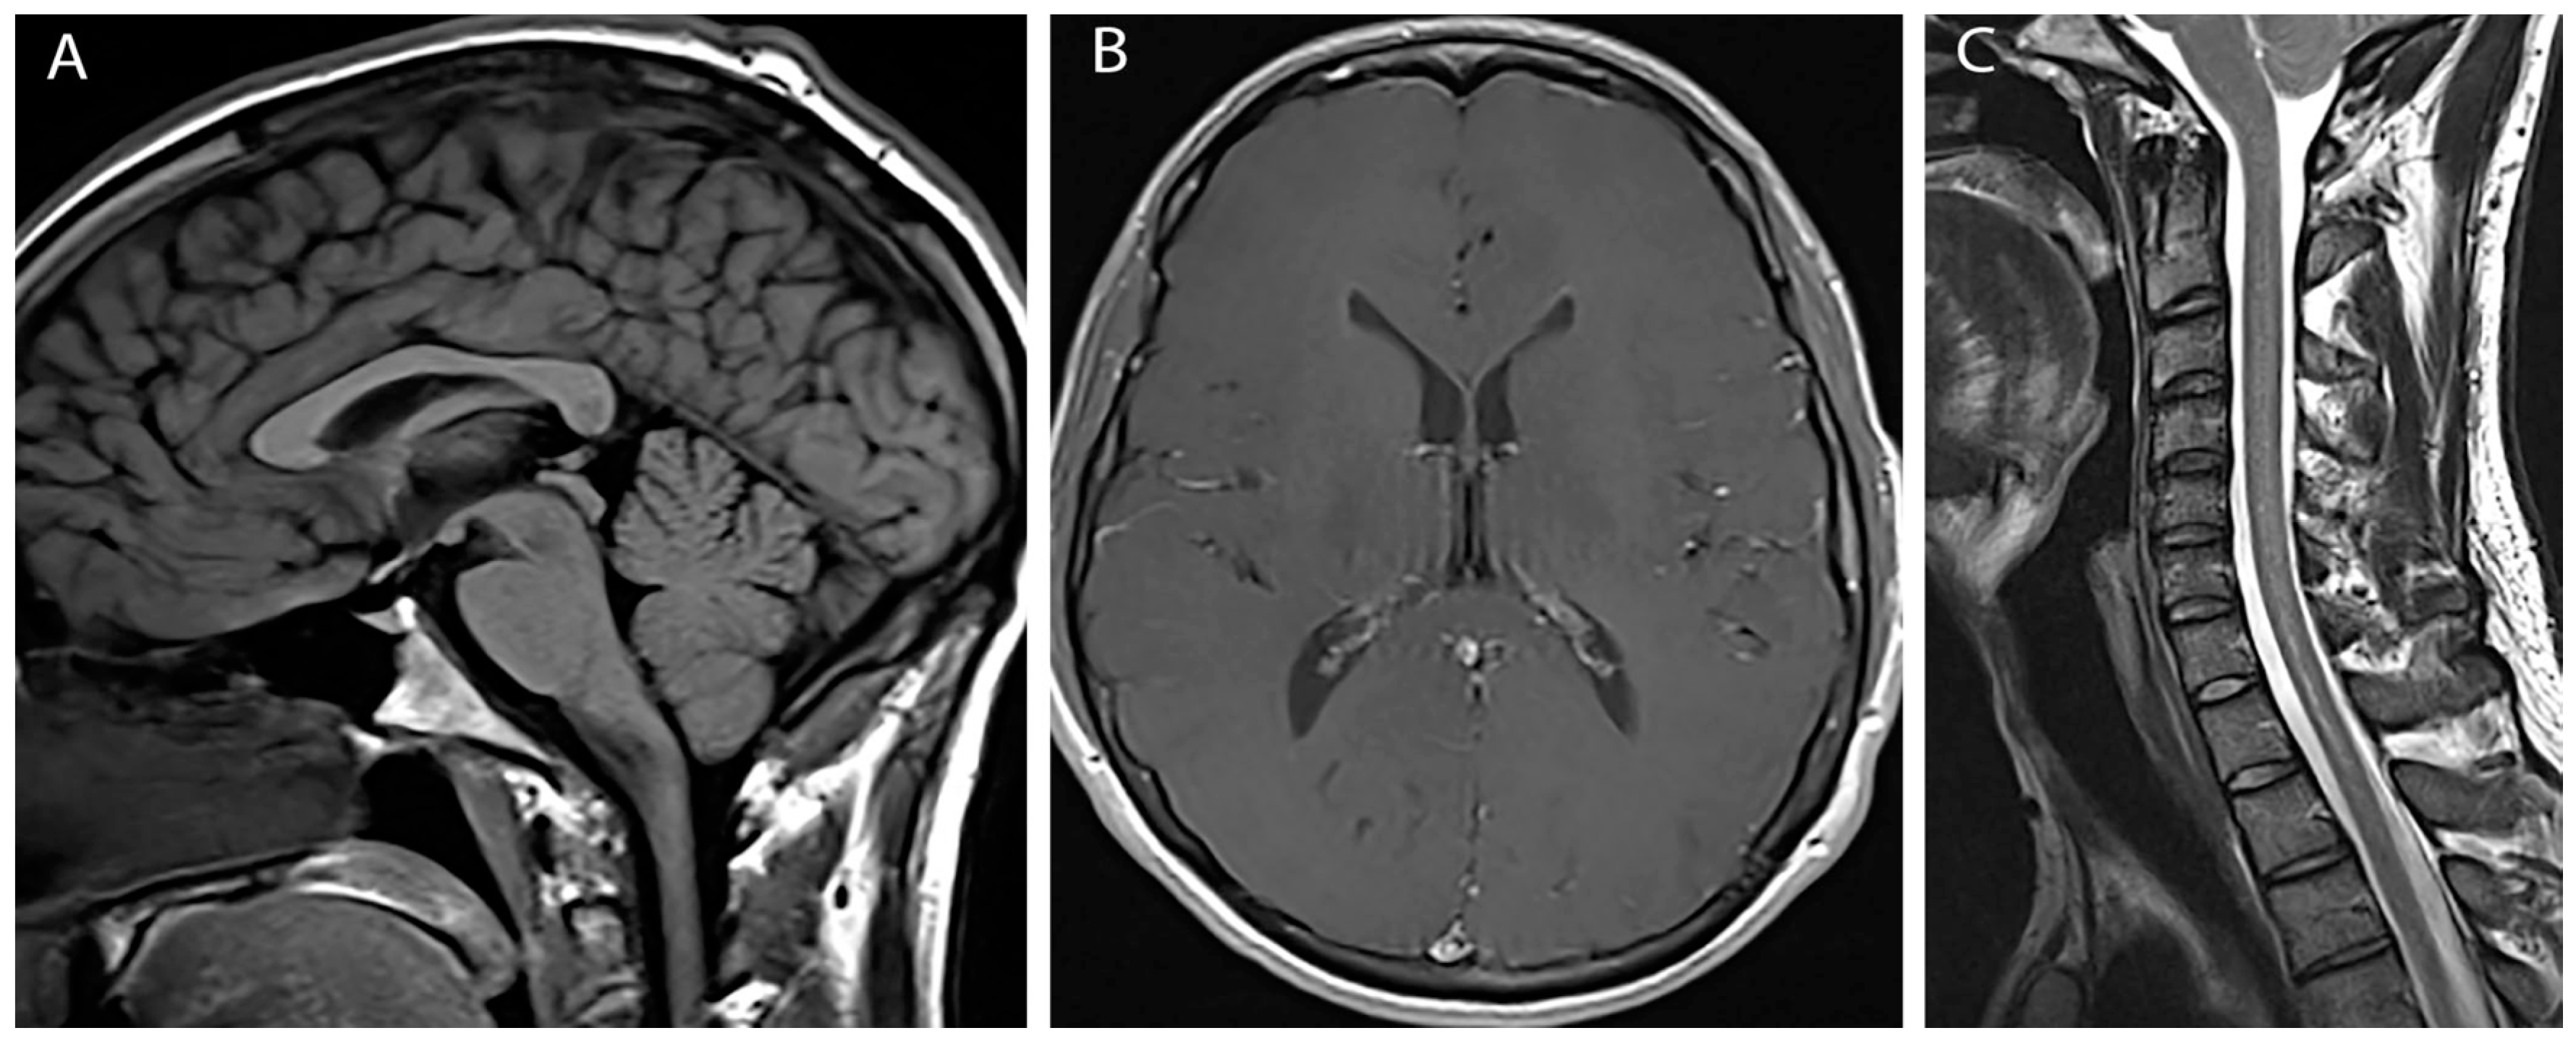

At three month follow up the patient reported modest improvement in headache symptoms. However, he had subsequently developed bilateral hand weakness and upper thoracic back pain. Physical exam was notable for bilateral finger flexor weakness, intrinsic hand muscle wasting, tongue fasciculations and ankle clonus. MRI of the brain and cervical cord with and without contrast revealed diffuse pachymeningeal enhancement, sagging brainstem, low lying cerebellar tonsils (10 mm descent) with crowding at the foramen magnum, and venous engorgement of the cervical epidural space (Figure 1A,B). This constellation of findings was suggestive of intracranial hypotension. Additionally, there was diffuse spinal cord signal abnormality involving cervical and upper thoracic spinal cord to the level of T8-T9 with a small syrinx at T1-T2 and an epidural fluid collection in the mid-thoracic spine (Figure 1C).

Figure 1. Pre-treatment images (A) Sagittal T1 weighted image shows herniation of cerebellar tonsils below foramen magnum; (B) Axial post gadolinium image shows diffuse pachymengeal enhancement; (C) Sagittal T2 weighted image shows extensive cord edema and syrinx.